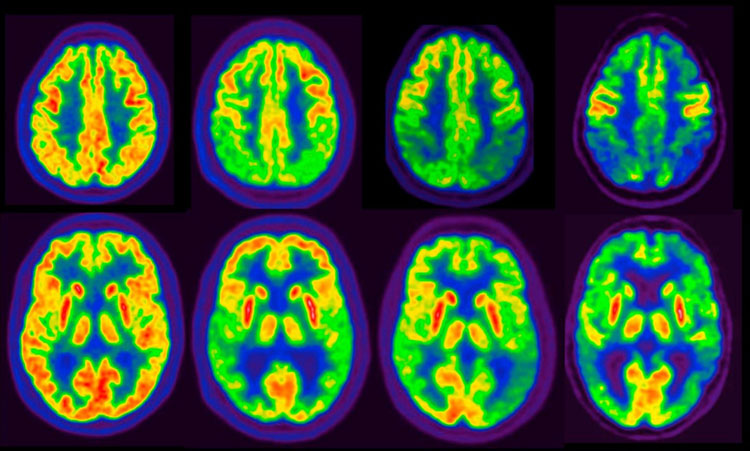

Si tratta di un particolare tipo di tomografia ad emissione di positroni concepita per studiare le malattie degenerative come l’Alzheimer in quanto in una particolare modalità è in grado di misurare la densità delle placche neuritiche di amiloide nel cervello di pazienti adulti con decadimento cognitivo